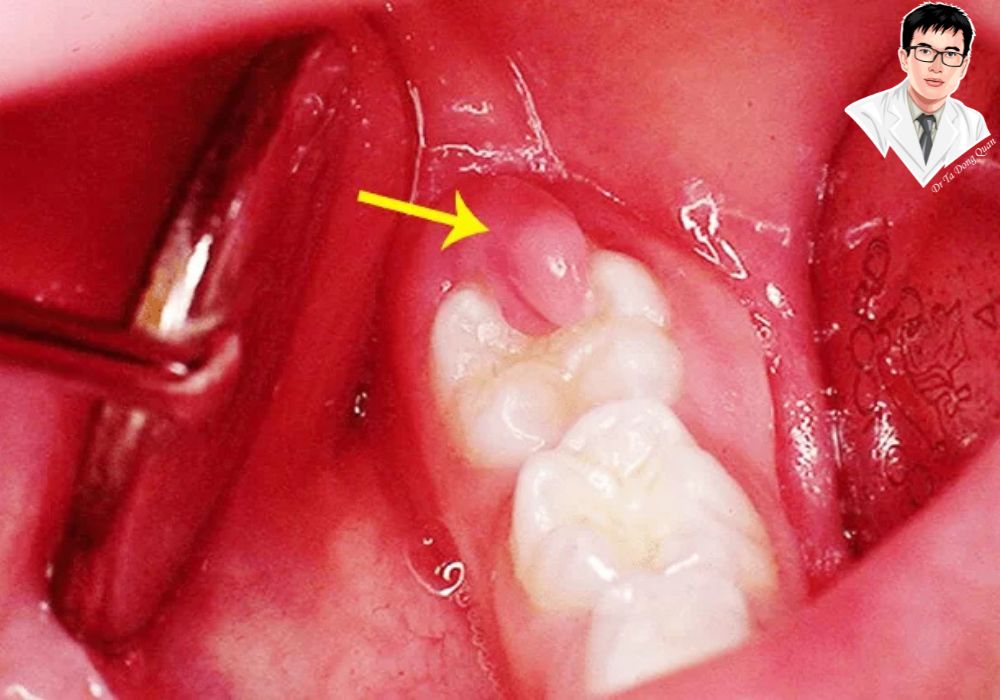

2. Những trường hợp được chỉ định cắt lợi

Những người có thân răng ngắn, viền nướu không đều, hoặc lợi phát triển quá mức thường được bác sĩ khuyên nên cắt lợi. Ngoài yếu tố thẩm mỹ, đây cũng là bước hỗ trợ trong các điều trị khác như bọc răng sứ hoặc chỉnh nha.

3. Tiến hành phẫu thuật cắt lợi

Bác sĩ sẽ sử dụng dao phẫu thuật hoặc tia laser tùy theo phương pháp đã thống nhất. Kỹ thuật được thực hiện cẩn thận để tạo viền nướu hài hòa, cân đối với nụ cười. Trong suốt quá trình, bạn hoàn toàn không cảm thấy đau, chỉ hơi ê sau khi hết thuốc tê. Đây là bước quan trọng nhất, ảnh hưởng trực tiếp đến kết quả và chi phí điều trị.